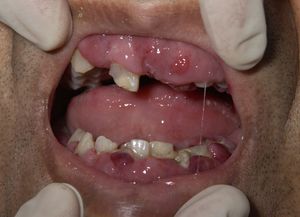

• 급성골수성백혈병(AML-M4)에서 백혈병 세포의 침윤으로 부어오른 치은. 단, 치은 부종은 다른 원인으로도 발생할 수 있다.

치은 부종: 특히 급성골수성백혈병(AML)의 특정 아형(M4, M5)에서는 백혈병 세포가 잇몸(치은)에 침윤하여 붓는 증상이 나타날 수 있다.[143][144]